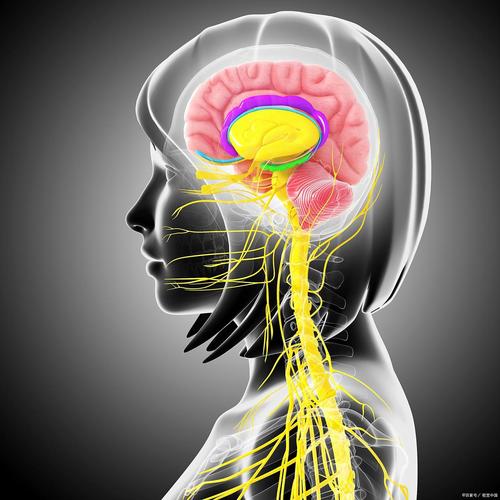

以下是新生儿中枢神经系统的主要表现,我将从正常表现和异常警示信号两个方面来详细说明。

正常的中枢神经系统表现

神经系统检查

医生在体检时会检查一些关键指标,以评估新生儿神经系统健康状况。

- 囟门:前囟门(头顶前部菱形的软区)约1-2厘米大小,平坦、轻微搏动是正常的,后囟门很小或已闭合。

- 瞳孔对光反射:用手电筒照射眼睛,瞳孔会迅速缩小,表明视神经和脑干功能正常。

- 肌力与肌张力:医生会活动婴儿的四肢,感受其抵抗力和活动范围。